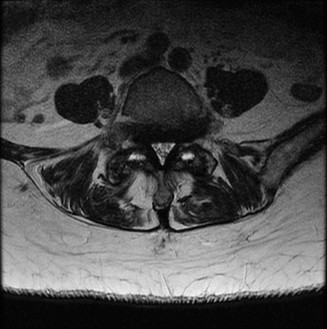

The correct answer is (A). The patient has a history that is consistent with cervical spondylotic myelopathy (CSM). Plain films confirm the presence of spondylosis. His history and examination indicates spinal cord dysfunction. The next study that should be ordered is an MRI of the cervical spine. A CT would be a reasonable alternative if the patient had a contraindication for MRI. That being said, a CT myelogram would be preferred. An EMG is not likely to be positive or useful in the diagnosis of myelopathy. A lumbar puncture is also not likely to be useful in making the diagnosis as there are usually no associated hallmark changes of the cerebrospinal fluid (CSF) in a patient with myelopathy. Advanced images of the patient’s cervical spine (Fig. 1–24) are reviewed. Of the following, which surgical treatment is most appropriate? 1. Laminectomy C3–6

Figure 1–24

The correct answer is (D). The sagittal T2-weighted MRI demonstrates a relatively lordotic spine with multilevel degeneration and cord compression at C3–4, C4–5, and C5–6. There is both anterior and posterior effacement of the CSF. Anterior or posterior procedures might be appropriate. Of note, a posterior procedure, such as laminectomy and fusion or laminoplasty is a reasonable option because of the preserved lordosis. In fact, it has been suggested that either procedure can be performed in a cervical spine with no more than 13 degrees of kyphosis. Effective posterior decompression relies on directly removing the posterior compressive structures (i.e., infolded ligamentum flavum, facet joints) and indirect decompression from the anterior structures (i.e., discs, vertebral body osteophytes) via the spinal cord drifting posteriorly. In this specific case, of the choices, laminectomy and fusion of C2–6 would decompress the stenotic segments. A laminectomy of C3–6 might achieve adequate decompression, but it is not recommended to perform a laminectomy alone as it may result in post-laminectomy kyphosis. An anterior cervical discetomy and fusion (ACDF) might be appropriate, but choice B does not include the most stenotic level, C3–4. Likewise, a corpectomy can be appropriate, but choice C does not include the most stenotic level.